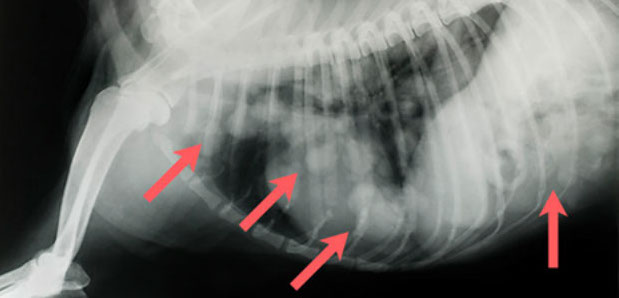

Mehrfachfrakturen nach Autounfall mit Lähmung der Hinterextremitäten, Hund

Knochenkot im Magen und Darm eines Hundes nach Grillparty